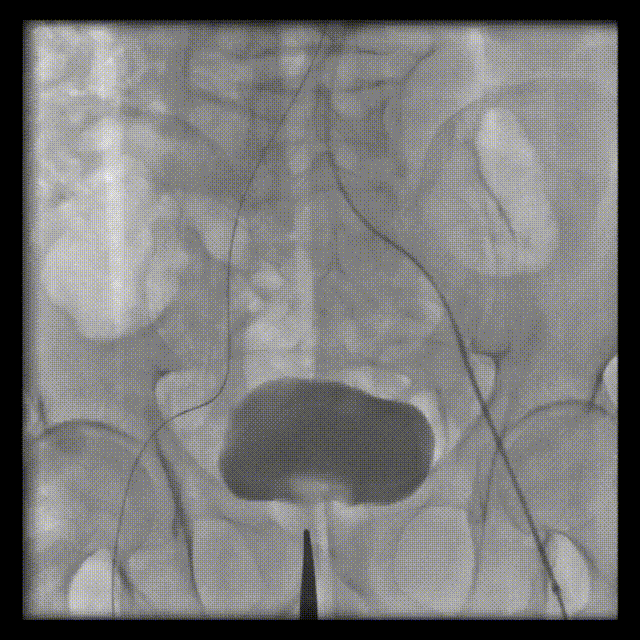

术前超声

术前CT